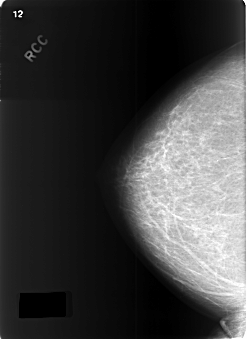

Digital Database for Screening Mammography

Volume: cancer_09 Case: C-0345-1

C_0345_1.RIGHT_CC

DATE_OF_STUDY 28 11 1997

PATIENT_AGE 59

DENSITY 2

RIGHT_CC LINES 5752 PIXELS_PER_LINE 4184 BITS_PER_PIXEL 12 RESOLUTION 50 NON_OVERLAY